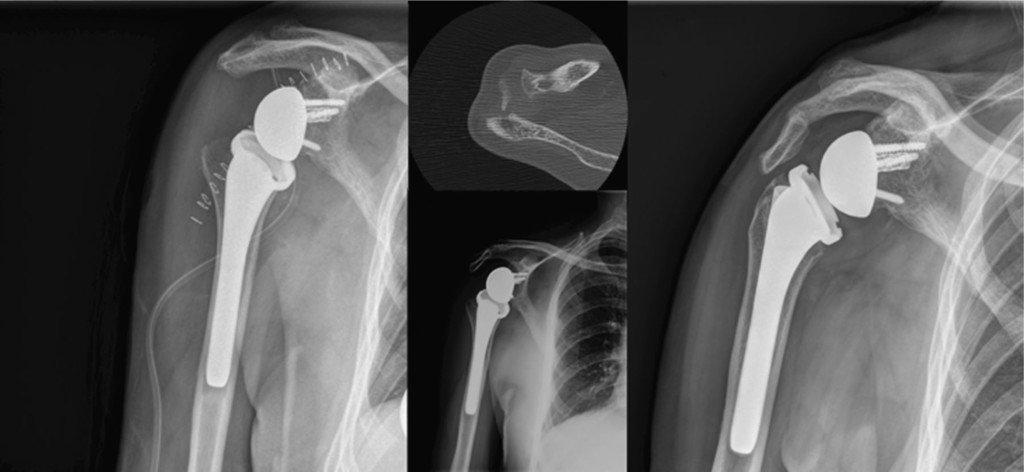

In a standard shoulder replacement, the ball of the joint is replaced with a prosthetic ball and the socket with a prosthetic socket. In reverse shoulder arthroplasty, the positions are switched — a metal ball is attached to the shoulder blade and a socket is attached to the upper arm bone. This design allows the deltoid muscle, instead of the damaged rotator cuff, to power the arm.